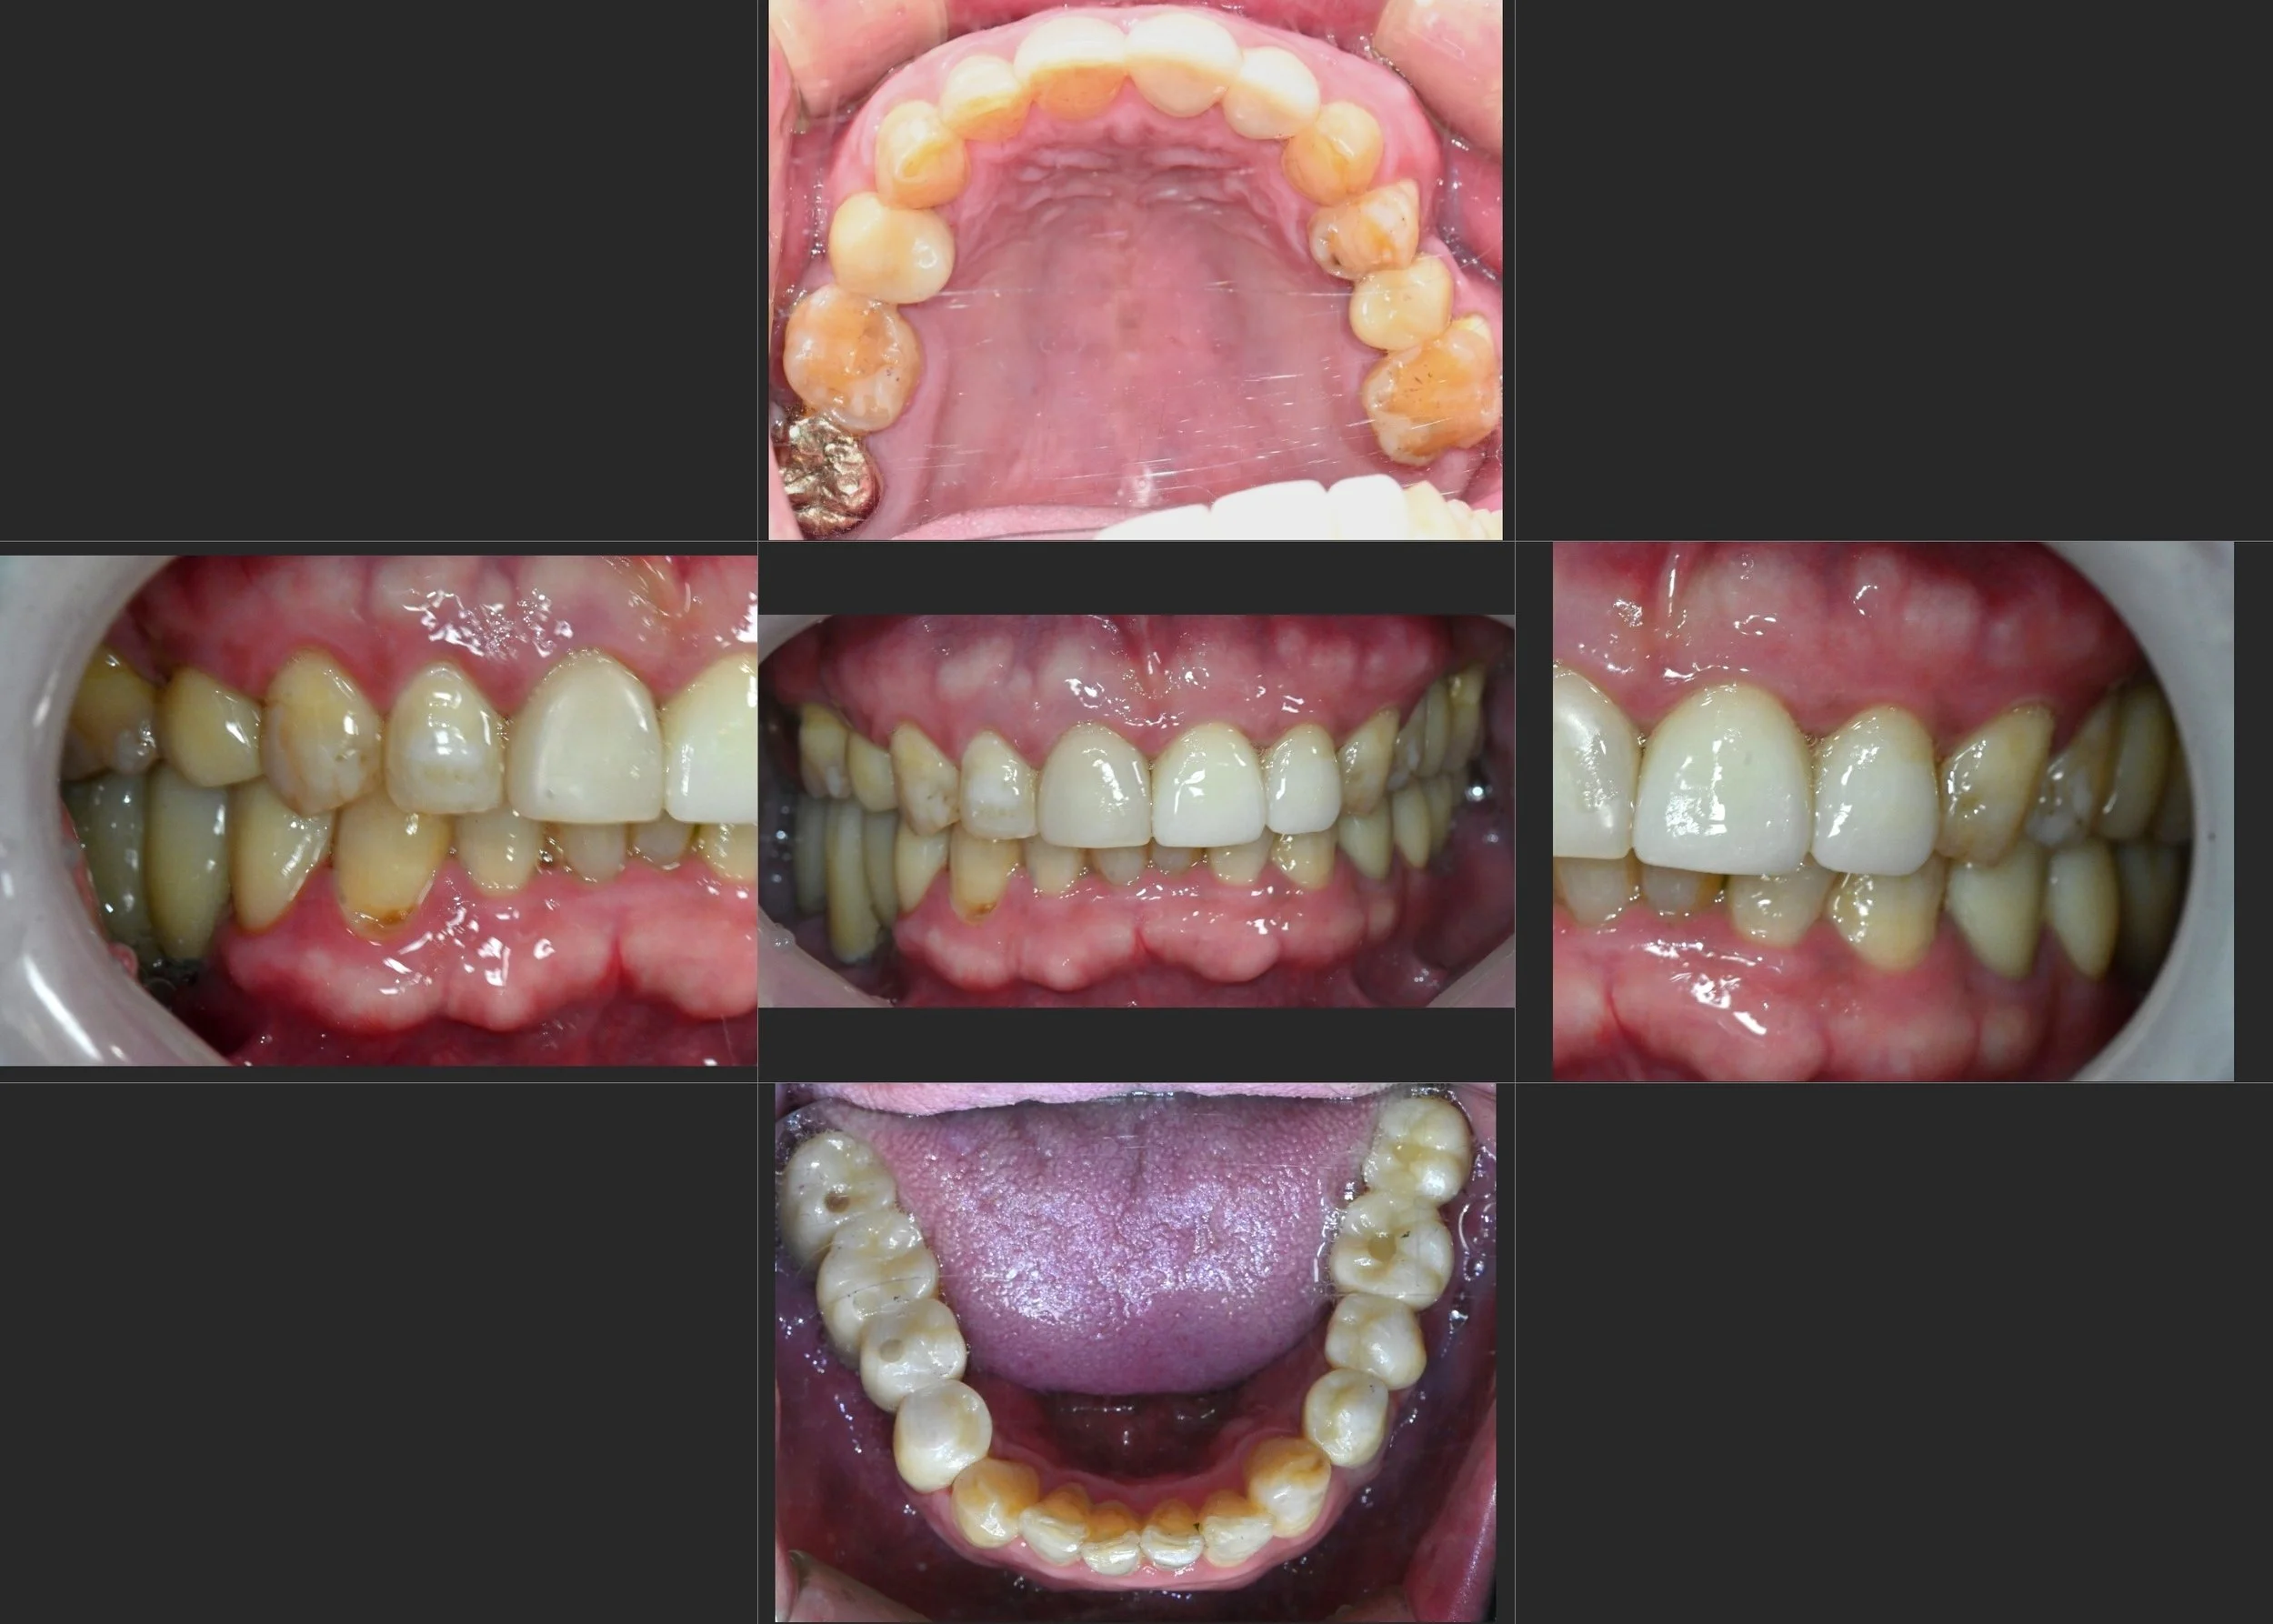

INTRA ORAL - BEFORE

A male patient in his 50s presented with multiple failing dental implants in the maxillary arch. The clinical situation was critical, characterized by:

• Failing and Lost Implants: Previous implants were non-functional or had been removed due to severe peri-implantitis and bone loss.

• Severe Alveolar Resorption: The supportive bone was highly compromised, both horizontally and vertically, particularly in the failing segments.

• Soft Tissue Atrophy: A lack of attached gingiva and shallow vestibule complicated future maintenance and prosthetic success.

• Occlusal Disharmony: With no stable posterior stops, the patient had completely lost functional occlusal balance.